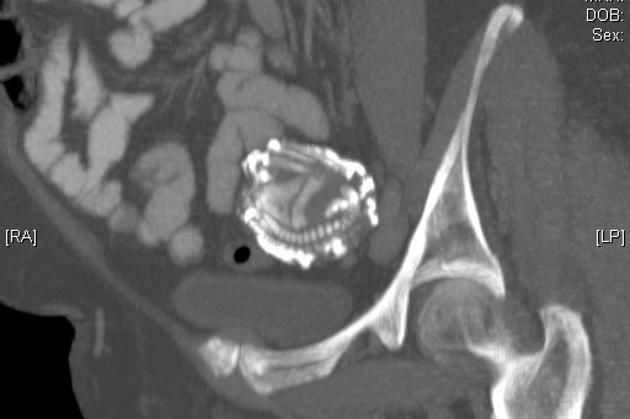

Μετά από μια μαγνητική τομογραφία, αποκαλύφθηκε ότι δεν ήταν όγκος, αλλά το μωρό της, το οποίο κουβαλούσε μέσα της από το 1955.

Αποδεικνύεται ότι το έμβρυο είχε σκάσει στην κοιλιά και μετατράπηκε σε ξένο σώμα για το ανοσοποιητικό σύστημα της μητέρας ενώ γύρω από αυτό σχηματίστηκε ένα ασβεστώδες κέλυφος.